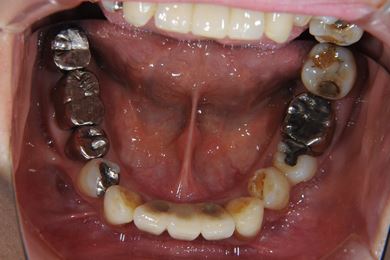

部分矯正治療+骨再生インプラント治療

| 性別/年齢 | 女性 / 52歳 | ||||||||||||||||||||||||||||||||

| 主訴 | 上前歯の歯並びが気になる | ||||||||||||||||||||||||||||||||

| 治療方針 | 全体的に骨が薄く、なるべく歯に負担を立てない治療計画にしました。口元も下げたいため、歯を少し細く削り後ろにさげました。部分矯正後、下顎のインプラントも併用しています。 | ||||||||||||||||||||||||||||||||

| 治療内容 | 部分矯正(唇側矯正ホワイト)、インプラント2本(GBR)、メタルボンドセラミッククラウン3本 | ||||||||||||||||||||||||||||||||

| 総治療費 | 1,573,951円 | ||||||||||||||||||||||||||||||||

| 治療期間 | 11ヶ月 |